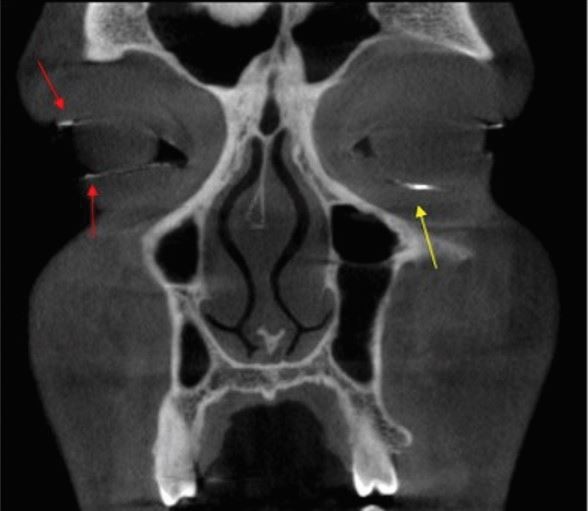

A 22-year-old male patient, Muslim by religion, underwent a CBCT scan for a suspected zygomatico-maxillary complex (ZMC) fracture. While evaluating the scan, the radiologist noted a well-defined linear radiopacity along the lower soft tissue margin of the left orbit and multiple radiopaque flecks along the upper and lower soft tissue margin of the right orbit (Fig. 1). Perplexed by the appearance of the radiopaque flecks, the radiologist examined the patient clinically. A foreign body was found in the lower left palpebral conjunctiva. When the patient was questioned about it, he revealed that he was applying surma to his eyes. He was asked to bring it to the next appointment. On examination, it was found to be a powdered particle (Fig. 2). The particle size was large enough to cause physical irritation to the conjunctiva.